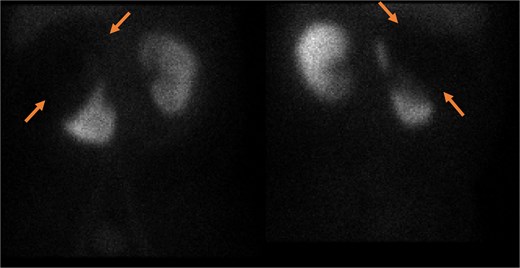

Ultrasound showed a large cystic lesion in the right kidney with internal debris and fluid–fluid levels (Fig. 1). Contrast-enhanced CT confirmed a thick-walled, fluid-filled cyst in the right upper renal pole without septations or calcifications—consistent with recurrent hydatid disease (Fig. 2). Incidentally, a small pelvic cystic lesion was seen adjacent to the rectum and seminal vesicle.

Gray-scale transabdominal ultrasound demonstrates a large well-defined anechoic lesion located in the upper pole of the kidney. The lesion contains internal, non-septated debris and shows no internal vascularity on color doppler imaging (a and b). Compared with previous right renal lesion showing collapsed membranes float within the cyst fluid, resembling water lily.